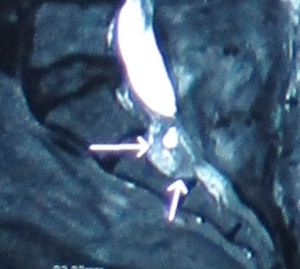

Tarlov cyst generally find at the first to the third section of the sacrum and is filled with cerebrospinal fluid. The swelling can gradually increase and cause the cauda equina nerve to be compressed, causing nerve root inflammation or myelopathy and even affecting the bony structures. Magnetic resonance imaging can clearly distinguish the location, size, and relationship with the dura and nerve roots of the sacral canal.